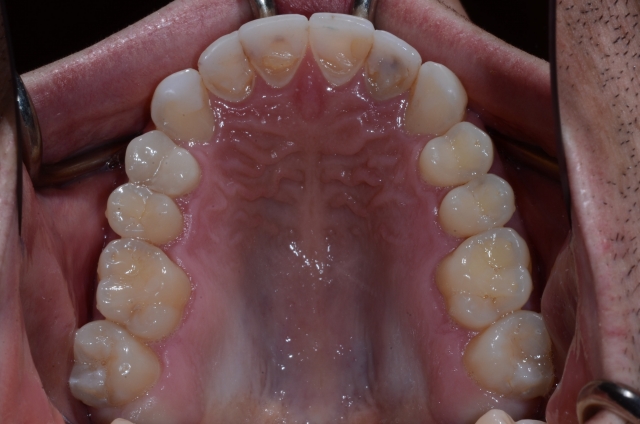

The first key to making this possible is that the teeth you’re dealing with must be smaller than the desired final size once they’re restored. This could be due to a genetic condition such as peg laterals (Fig. 1) or a case that involves excessive wear (Figs. 2–3).

Yes, you could consider placing crowns on all the latter patient’s teeth and restore him that way. He is very young and clearly had significant functional issues, so I don’t know about you, but that makes me really nervous — and not only because I feel there’d be a high risk of him breaking porcelain. Think about it: He is destroying his teeth and he’s also destroying his wear guard, as seen in Fig. 4.

In a case like this, when pretty much all the teeth are worn (yet still in the right position), you can add to them, restoring what has been worn away and at the same time adding a protective layer. Yes, you would prepare the teeth lightly to gain defined margins, but I would argue that if you pick the right restorative materials, you don’t even have to do that in this case.